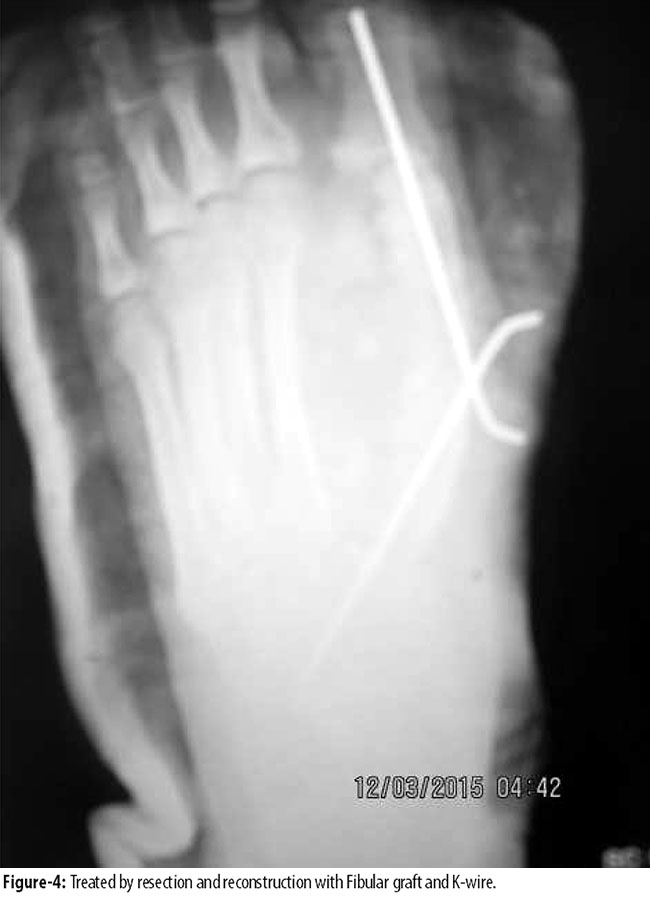

Duration of symptoms ranged from 4 to 12 months with a mean of 6.54 months (SD 4.08). All the tumours presented as expansile lesion, destroying cortex in 8(3.3%) cases. In all cases, lesion was more than half the diameter of the bone and thickness of sub-chondral bone in adjacent articular surface was less than 5mm to 0mm. All of them had extension into the soft tissue. Open biopsy was performed in 7(2.9%) cases. In 6(2.5%) cases, fine needle aspiration cytology (FNAC) was diagnostic, showing giant cell lesion. 1(0.4) calcaneal giant cell tumour was treated by extended curettage and filling the cavity with fibular head compact bone graft. Other 2(0.8%) cases of calcaneal giant cell tumour were treated by complete resection of calcaneus. 1(0.4%) case of talus GCT was treated by curettage and bone grafting. Out of 7(2.9%) cases of metatarsals, 4(1.6%) were in 1st metatarsals, 2(0.8%) in 2nd metatarsal and 1(0.4%) in 3rd metatarsal. 2(0.8%) GCTs in 1st metatarsal (Figure-3 and 4)

and 1(0.4%) in 2nd metatarsal were in stage3 (Figure 5 and 6),

and were treated by en-bloc resection and reconstruction with free fibular graft. Fibular graft was held with intramedullary K-wire. Rest of the tumours in all metatarsals were stage 2 and were treated by curettage and autologous cancellous bone grafting. In 2(0.8%) cases of phalanges, 1(0.4%) in proximal phalanx of big toe was treated by resection and fibular bone grafting and 1(0.4%) was treated by amputation of 3rd toe. There was 1(0.4%) recurrence in calcaneus and 1(0.4%) in 1st metatarsal, both of which were initially treated by curettage and bone grafting. Calcaneus recurrence was treated by below-knee amputation and 1st metatarsal recurrence by resection and iliac crest cortico cancellous bone graft.